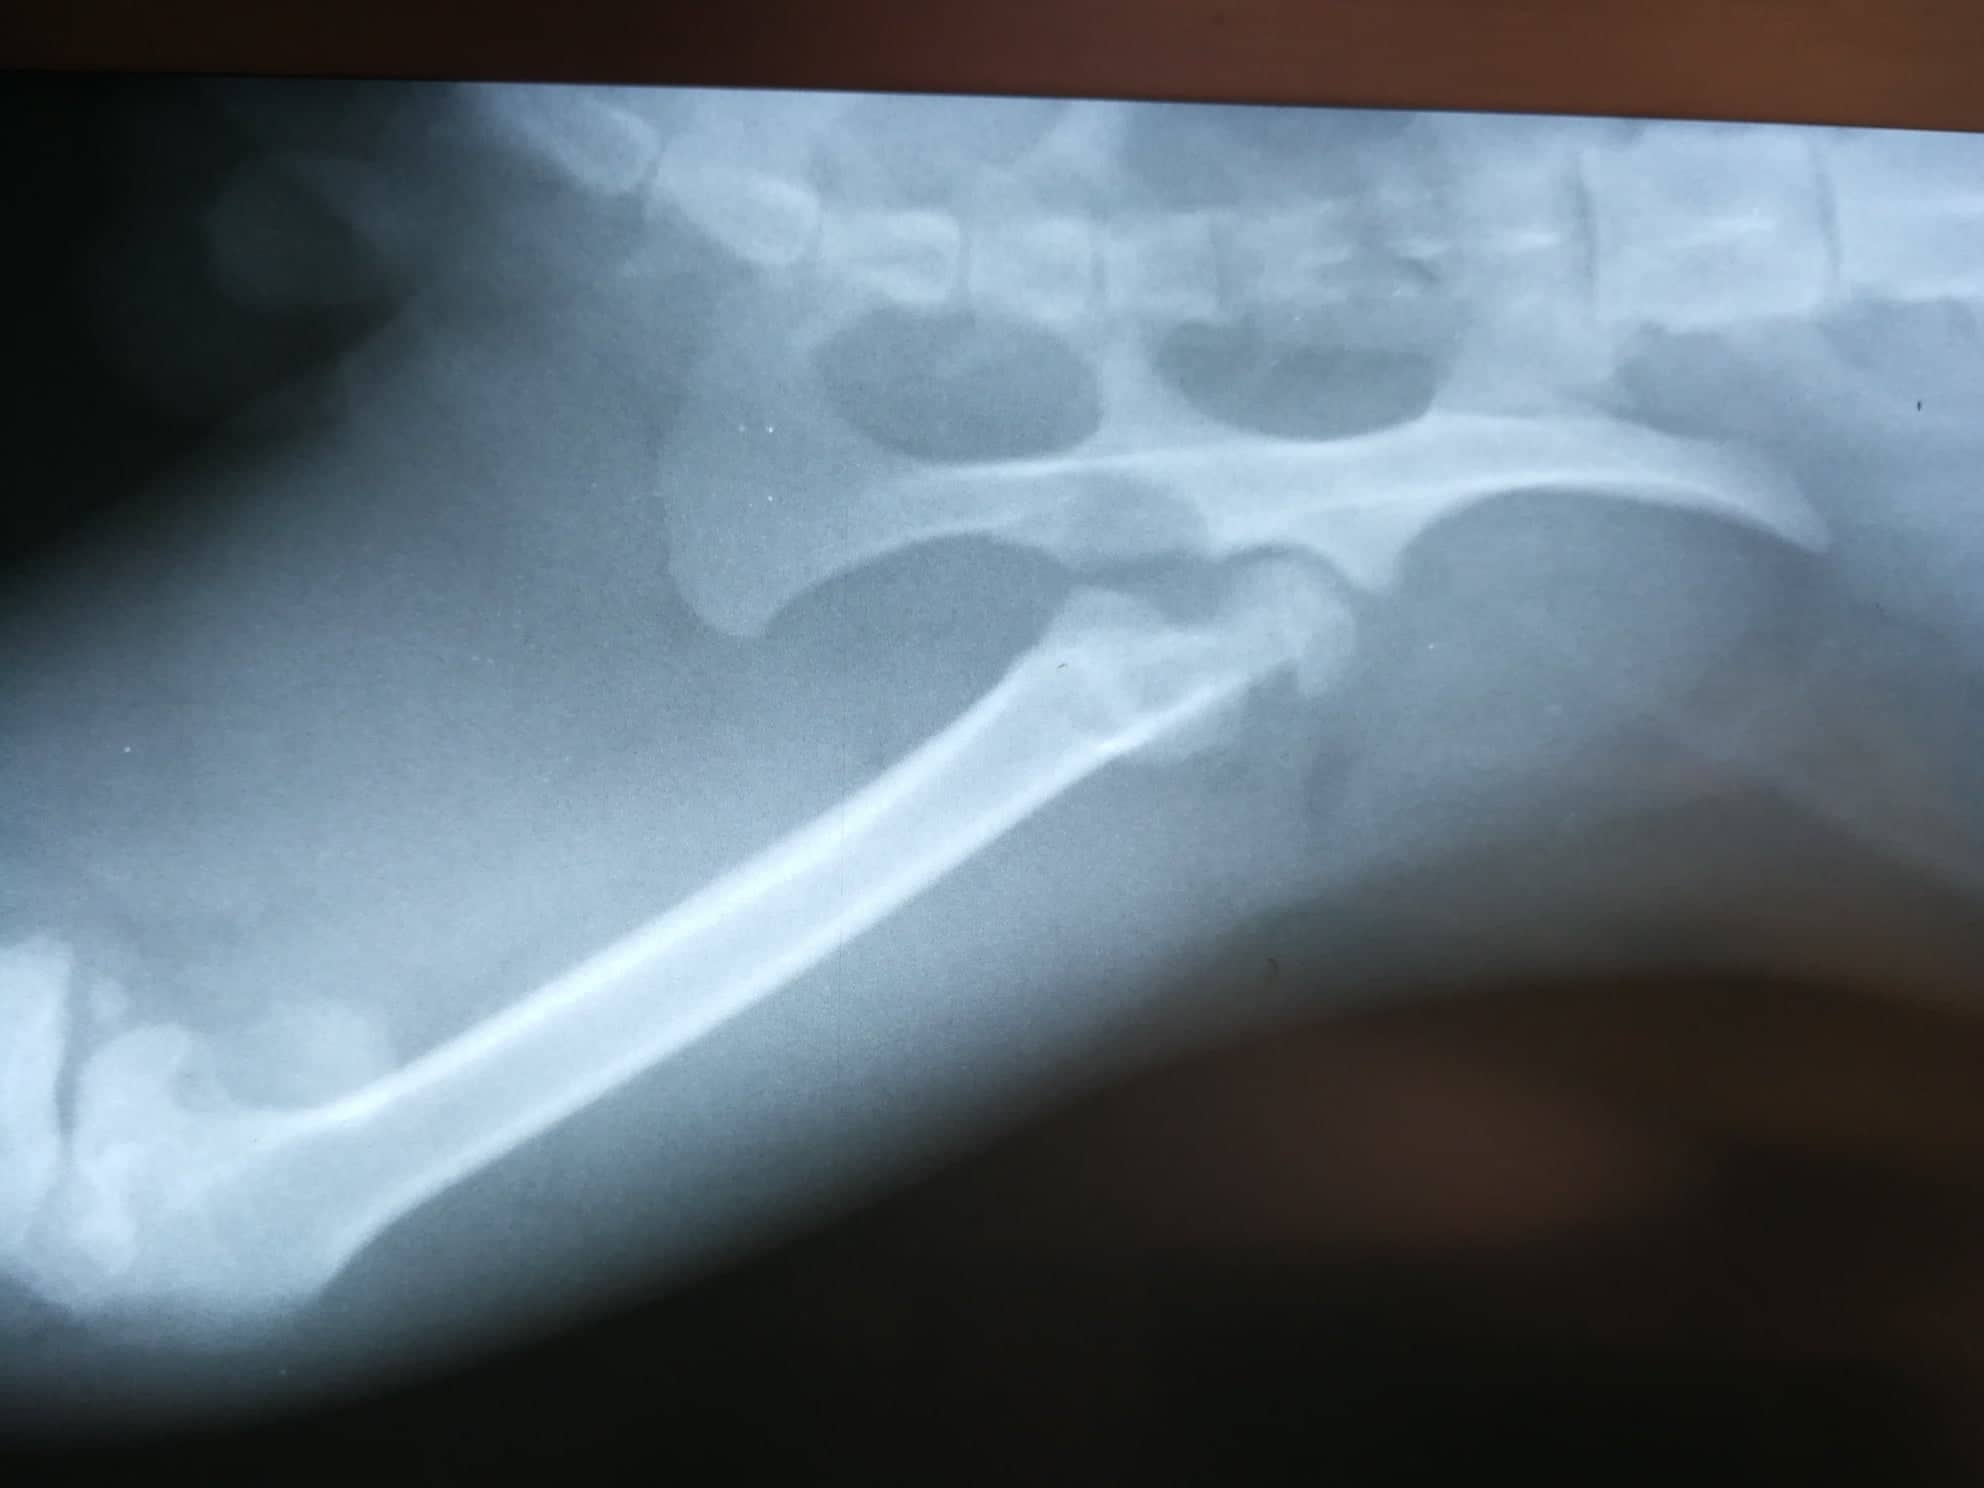

Rentgen ukázal, že Puzzle měl starou zlomeninu nohy a k tomu vykloubenou kyčel. Kocourek měl zal sebou jistě hodně bolesti… Dělali jsme vše pro to, aby vyhrál svůj boj a dostal svou šanci najít si novou rodinu a mít konečně milující páníčky.

Nejdřív bylo nutné Puclíkovi dát do pořádku kyčel. Operace dopadla dobře. Pak ale bylo potřeba ještě opravit zlomenou zadní packu. Pan veterinář kocourkovi nožku krásně zpevnil. Mysleli jsme, že to byla Puclíkova poslední překážka na cestě ke šťastnému životu plnému rozmazlování…